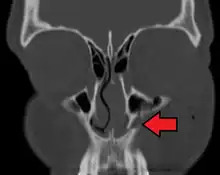

- The body of the maxilla: pyramid-shaped; has an orbital, a nasal, an infratemporal, and a facial surface; contains the maxillary sinus.

- the maxillary sinus

The maxillary sinus appears as a shallow groove on the nasal surface of the bone about the fourth month of development, but does not reach its full size until after the second dentition.

The maxillary sinus presents the appearance of a furrow on the lateral wall of the nose. In the adult the vertical diameter is the greatest, owing to the development of the alveolar process and the increase in size of the sinus.